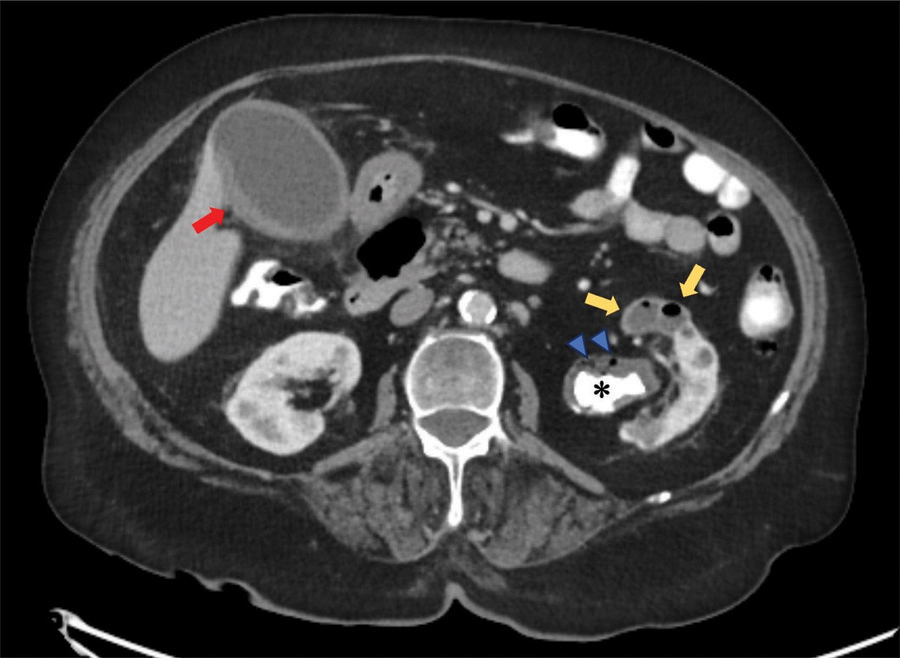

CT displayed a staghorn calculus (Figures 1 and 2, *) in the largely atrophic left kidney. There was a mild dilatation of the renal pelvis and calyces with wall thickening and multiple rounded fluid density cavities in the parenchyma. Gas bubbles were present in the renal pelvis surrounding the staghorn calculus (Figures 1 and 2, blue arrowheads). Some of the collections in the renal parenchyma contained gas-fluid levels (Figure 1, yellow arrows). A candidiasis infection (Candida glabrata >100 000 KVE/ml) was also identified on the urine culture test.

Figure 1

CT abdomen - axial plane.

In addition, there was a diffusely thickened and hyperemic wall of the gallbladder, consistent with acute cholecystitis (Figure 1, red arrow). The right lower lobe pneumonia was depicted on the coronal view (Figure 2, red arrowhead).